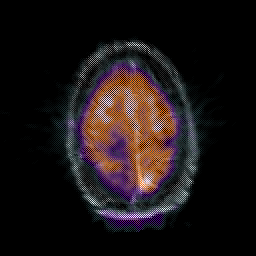

Glioma Overlay -- Slice #18

[Home][Help][Clinical] Slice 18